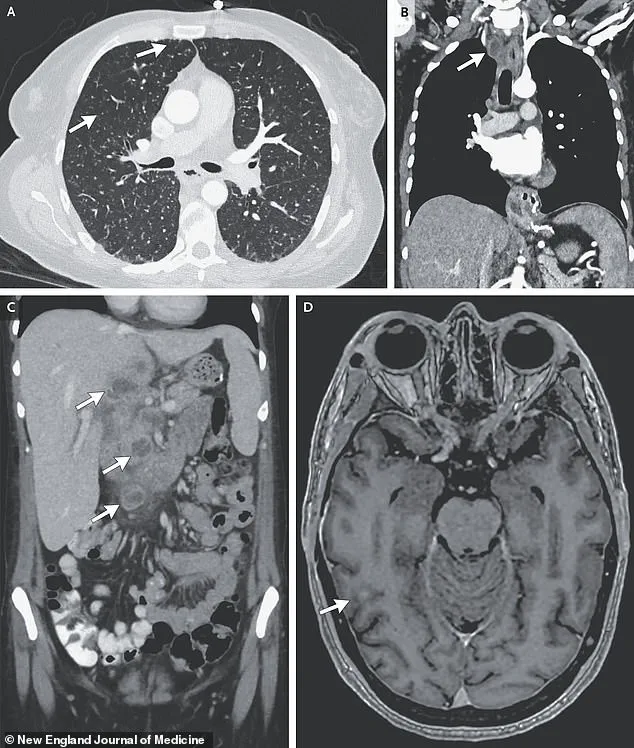

X-ray scans of the woman’s lungs revealed small nodules, a red flag for bacterial infection.

Further imaging and biopsies uncovered lesions in her liver, lymph nodes, pancreas, and brain—indications that the infection had spread far beyond the lungs.

Medical scans revealed nodules in her lungs, an enlarged lymph node, and lesions in her liver, pancreas, and brain—evidence of a TB infection that had spread far beyond its usual confines.